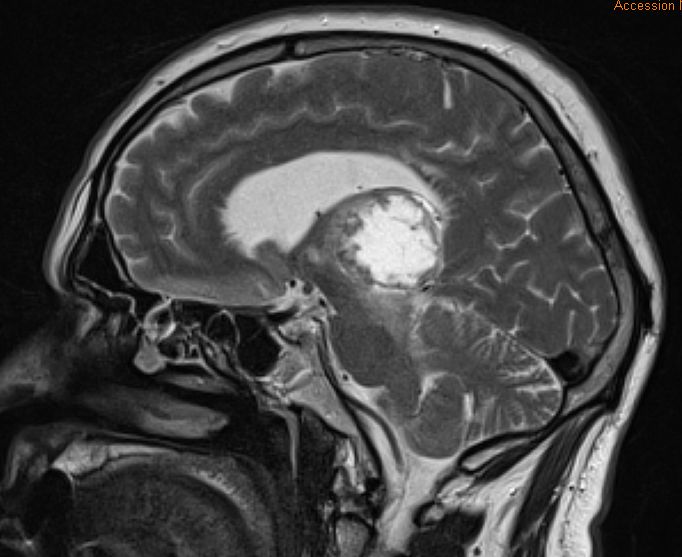

| Thalamus | 59jähriger Patient mit schlecht differenziertem

Adenokarzinom des linker Oberlappens cT2b pN1 M1b (pul, bra). Latente

Armparese links und Feinmotorikstörung der linken Hand. Keine

Sensibilitätsstörung, Sprachstörung, kognitive Defizite. Große Metastase in

rechten Thalamus.![]() | |||